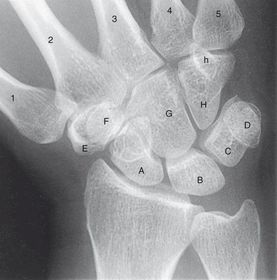

Radial Deviation